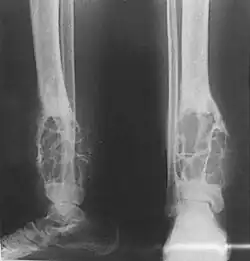

X-rays of the affected area show a well defined tumour in bone, with multiple lobules giving a "soap bubble" appearance.[9] MRI can provide a more useful guide to its severity.[9]